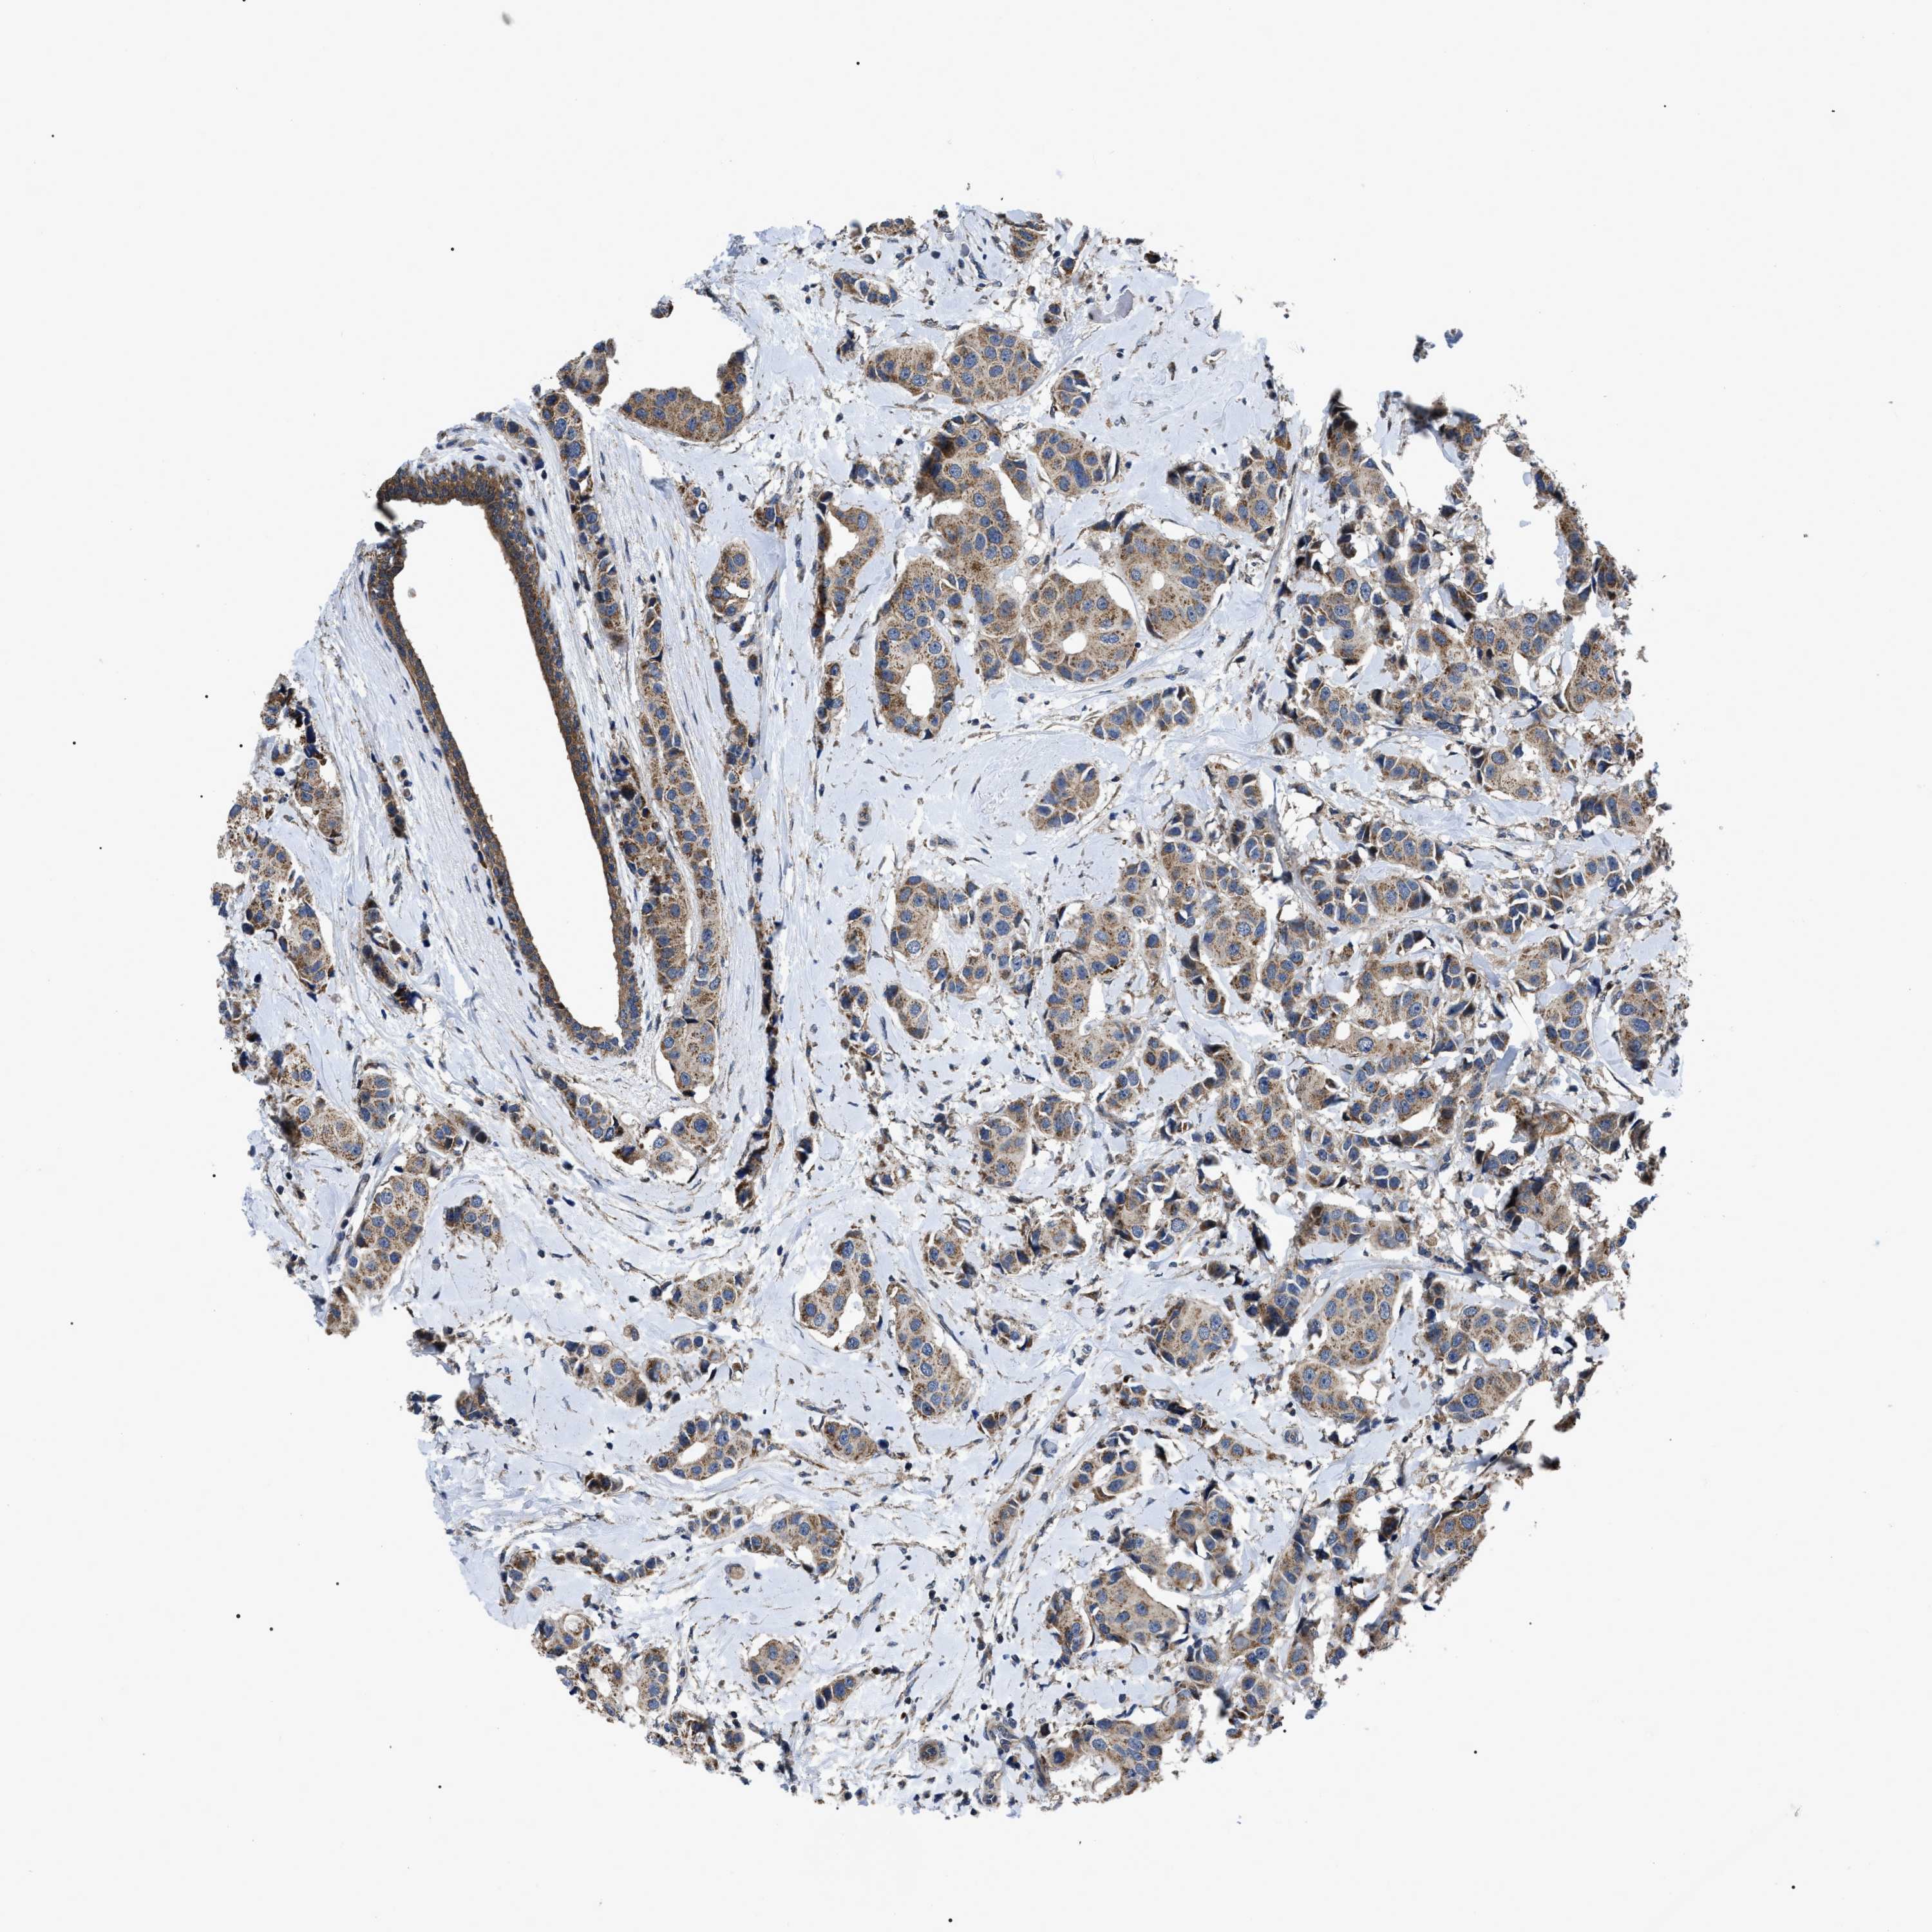

CANCER BREAST CANCER Show tissue menu

BRCA TCGA BRCA VALIDATION PROTEIN EXPRESSION